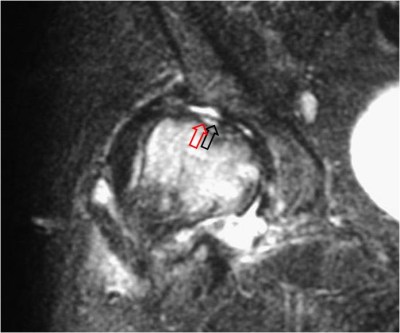

SIGNO DE LA DOBLE LÍNEA

Signo de osteonecrosis avascular visible en la resonancia magnética, en imágenes potenciadas en T2. En la osteonecrosis avascular se ve una línea de alta intensidad de señal rodeada por un anillo paralelo de hiposeñal, con frecuencia de bordes serpiginosos. La línea hiperintensa (flecha negra) corresponde a tejido de granulación hiperémico y la línea externa hipointensa (flecha roja) corresponde a hueso escleroso.